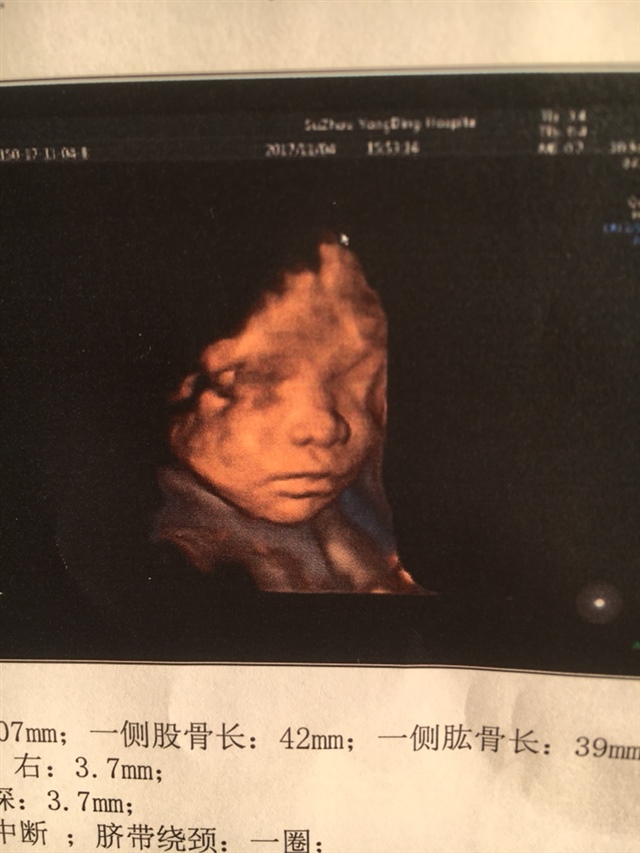

33周我的绕颈两圈

A丫丫童装😛[帖主]:宝爸看到四维单子一个劲的说不好看、不好看…😅